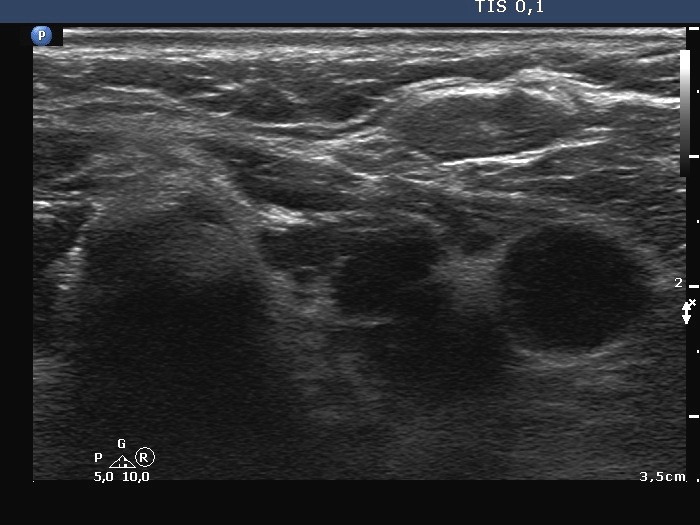

Ultrasonography. The thyroid was hypoechogenic and atrophic. The left lobe was composed of hypoechogenic areas partly divided by connective tissue. There were no nodules of pathological sense in the thyroid.